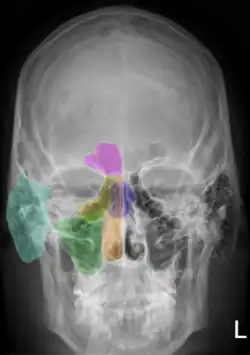

Sinus frontalis (lila)

Sinus sphenoidalis (gelb)

Sinus maxillaris (Zugang in Bildmitte)

orange: Cavum nasi

grün: Sinus maxillaris

gelb: Cellulae ethmoidales

lila: Sinus frontalis

blau: Sinus sphenoidalis

zyan: Processus mastoideus